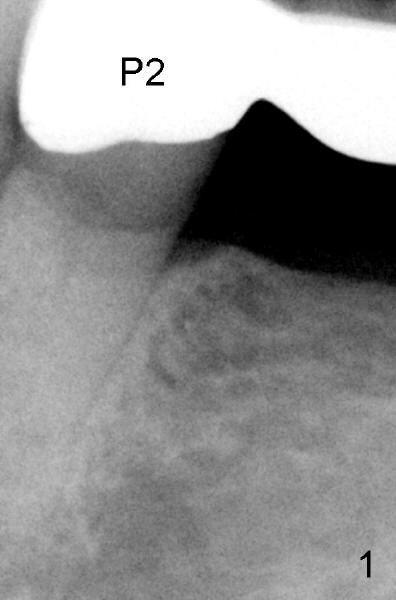

七十岁童太太因左下第二前磨牙(基牙)游走性牙痛就诊,有明显扣痛,第一前磨牙扣痛稍轻,仔细检查发现第二前磨牙颈部缺损,穿髓。开髓证实牙髓坏死,根管口椭圆形,颊舌侧宽,怀疑有舌侧第二根管,但是最后后者好像融合于颊侧根管。图一是五年前拍摄的根尖片(P2:第二前磨牙),图二最近拍摄的:根管治疗前,但是没有拍摄第二张angled PA,图三术中:插入主牙胶尖40/.06,不到19.5毫米(离根尖2.45毫米),一般使用Apex locator决定working length,但是从PFM retainer开髓,Apex locator非常敏感,插入塑料小管也不好用,只好凭手感决定working length。当术中根尖片拍摄后,努力增加一些working length,但是没有特意弯曲细的根管扩大针,图四显示根管治疗完毕,working length19.5毫米,使用cold condensation,离根尖1.58毫米,用树脂封闭根管治疗开口。

根据术前PA图1,2和术后PA图3,4比较,RCT的P2有术后的wide apical PDL,提示有根尖炎症。另外,P2的根管Cleaning,Shaping和充填没有至根尖孔,会增加P2 RCT 失败的可能性。从4张PA中,我没有看到有另外的根管存在,至少在apex 以上的牙体没有发现,但你仍可多拍几张前后45度的X-ray看看,牙体的CT不是Standard of Care, 业界需时才能普遍接受,且另外收费,病人会拒绝,但如可能scan一下 It doesn't hurt.